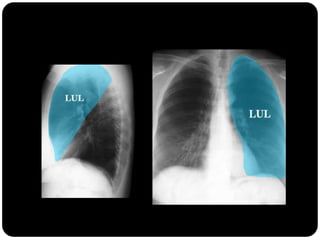

Qual lobo está afetado? Por quê?

Língula pois borra

contorno cardíaco

esquerdo

Em que lobo está essa lesão?

Resposta: LID

Importância do

perfil;

Importância da

ausência do sinal da

silhueta;